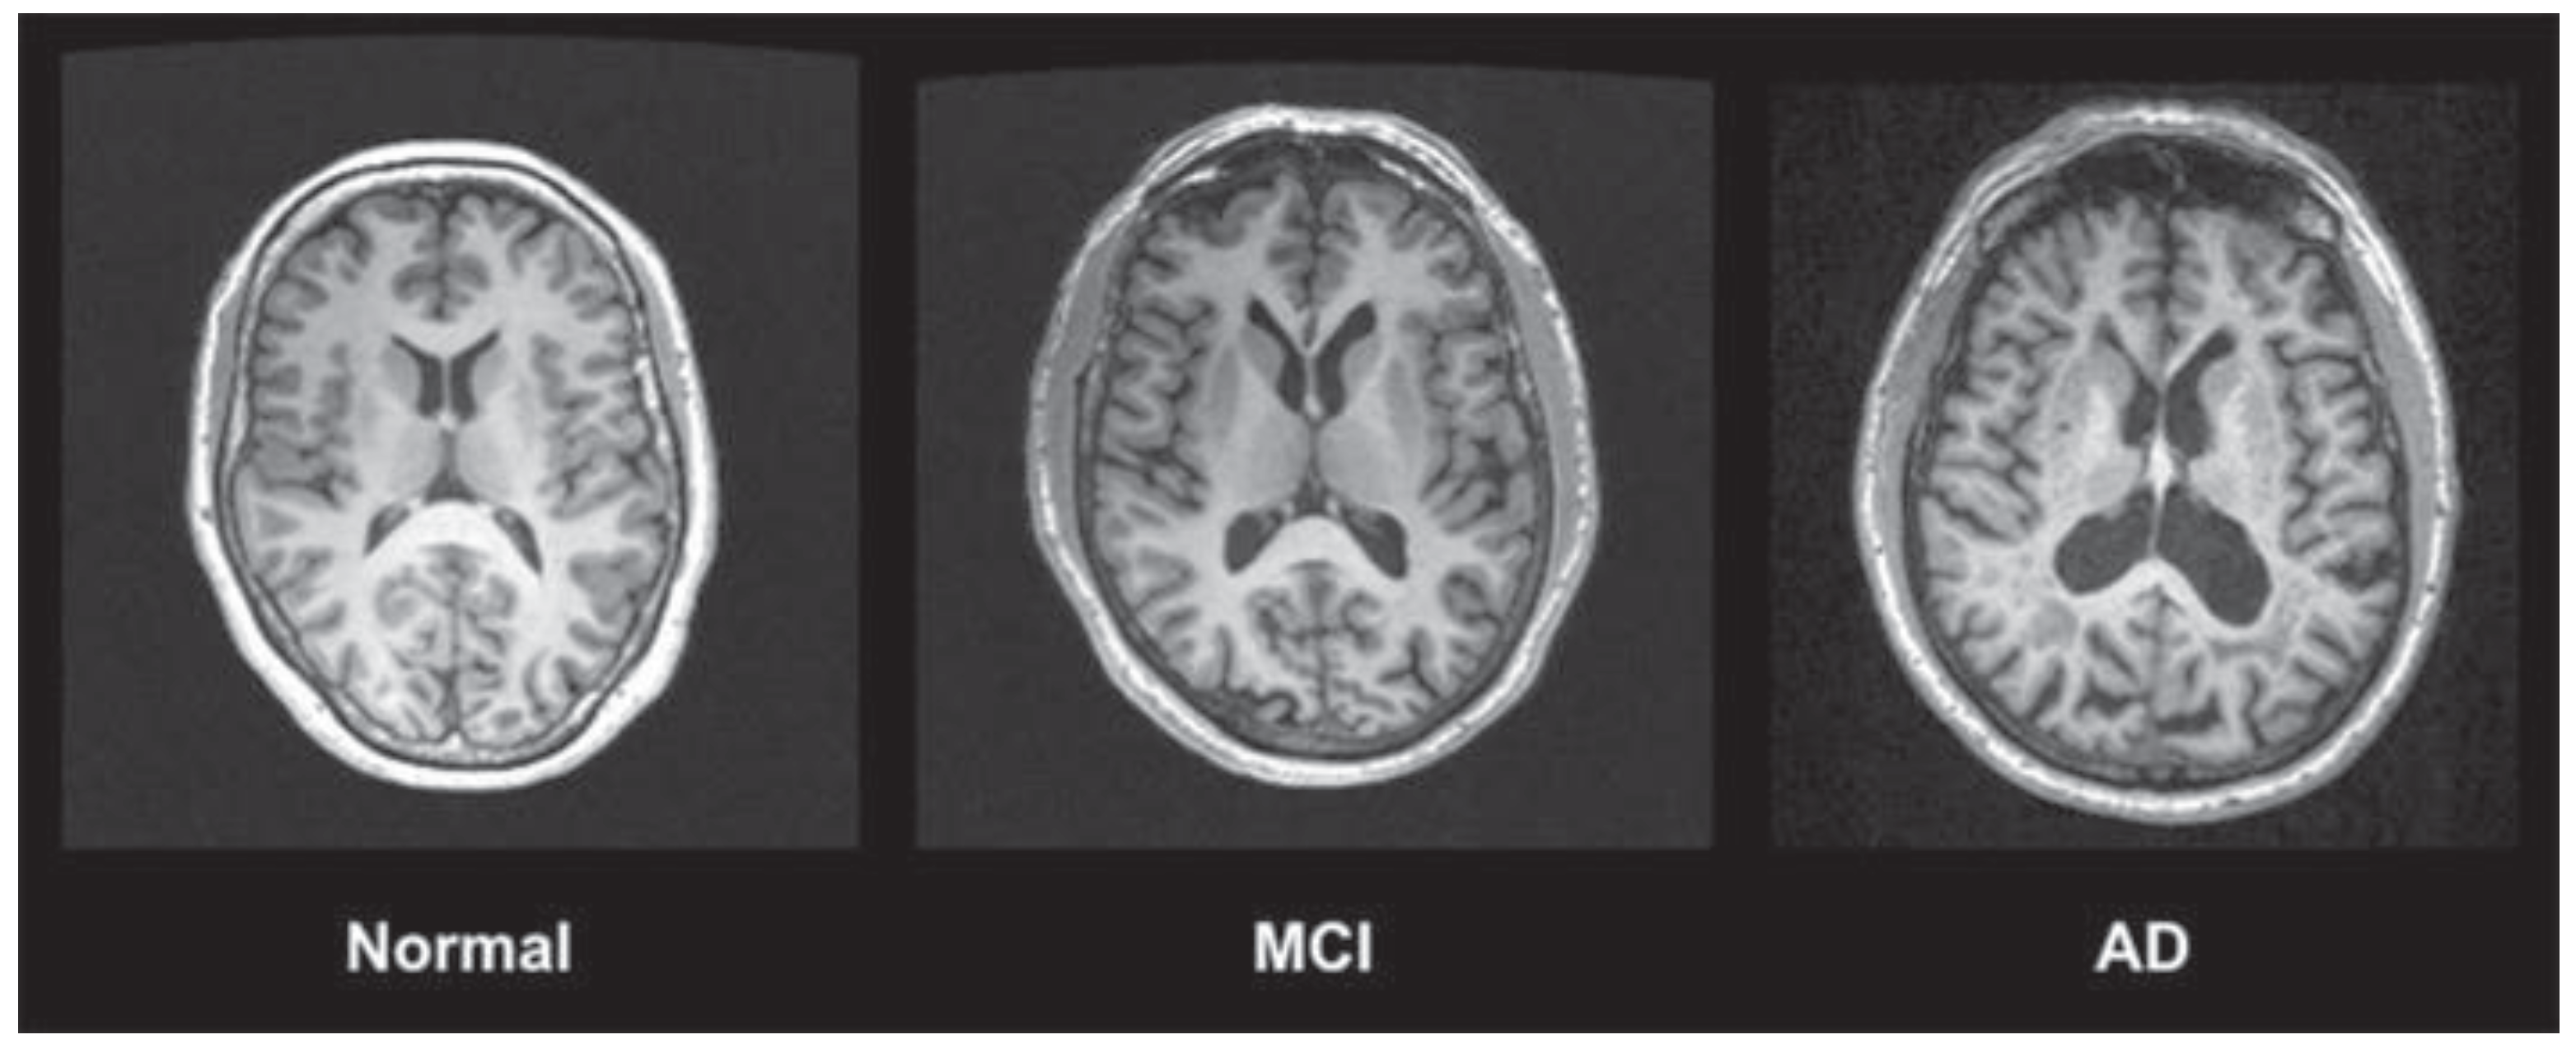

- Chandra, A.; Dervenoulas, G.; Politis, M. Magnetic resonance imaging in Alzheimer's disease and mild cognitive impairment. J. Neurol. 2019, 266, 1293–1302. [Google Scholar] [CrossRef] [PubMed]